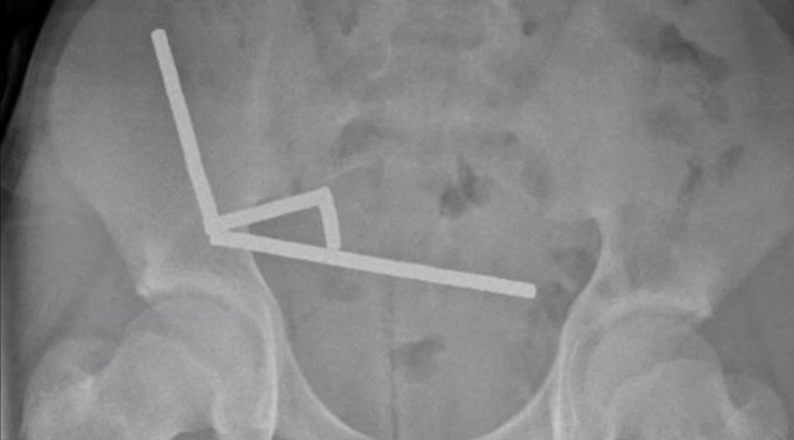

X光影响照片。Lekamalage et al., NZMJ, 2025

通过X光检查,医生在男孩肠道的不同部位影像中发现了四条线性磁铁链。这些小型金属物体进入腹腔后,以破坏性的方式聚集在一起。